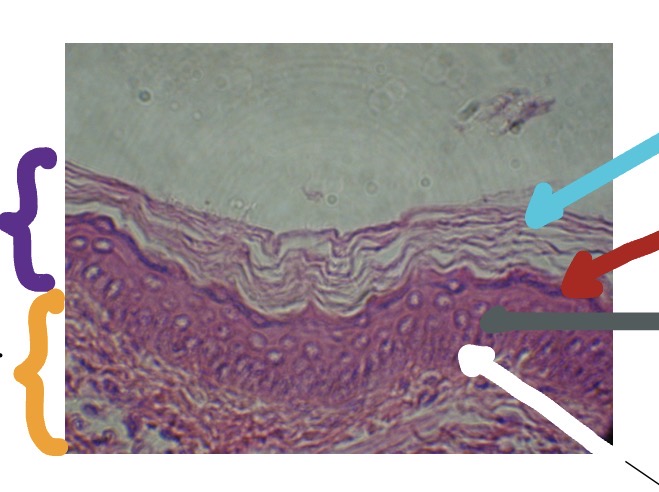

<p>What’s the purple line for this photo?</p>

What’s the purple line for this photo?

Epidermis

<p>What’s the orange line for this photo?</p>

What’s the orange line for this photo?

Papillary Layer of Dermis

<p>What’s is the blue line in this photo</p>

What’s is the blue line in this photo

Stratum Corneum

<p>What is the red line in this photo</p>

What is the red line in this photo

Stratum Granulosum

<p>What is the grey line in this photo</p>

What is the grey line in this photo

Stratum Spinosum

<p>What is the white line in this photo</p>

What is the white line in this photo

Stratum Basale